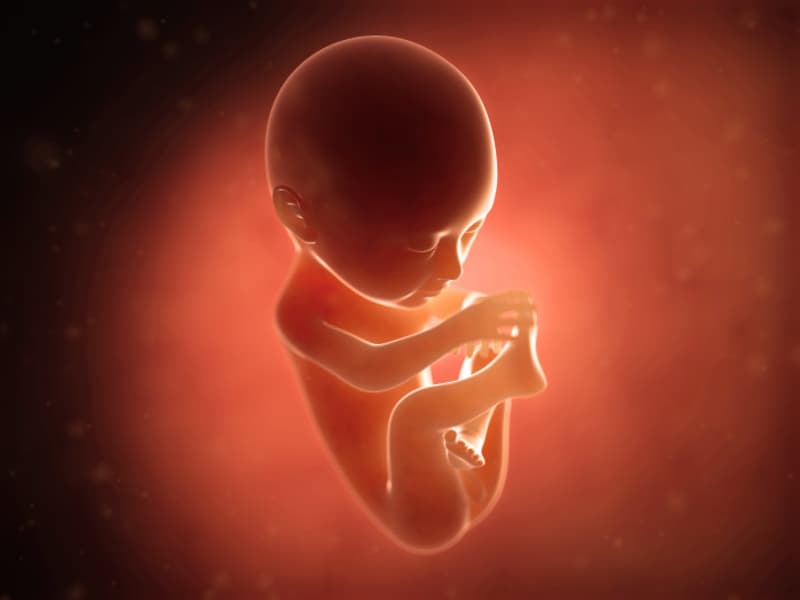

妊娠 21 週目の間、胎児は成熟し、成長を続けます。母親と子供の両方の発達の進歩と体の変化に関しては、21週目も例外ではありません。

あなたの赤ちゃんは現在、バナナほどの大きさで、身長約7インチ、体重約11オンスです。

赤ちゃんのサイズは大きくなっていますが、この段階でも子宮内にはまだ動ける余地がたくさんあります。

その他の変更点は次のとおりです。

- 急速な脳の成長

- 軟骨が骨に変わり、骨格が硬化し、 骨髄での血球の産生が始まります。

- 柔らかい頭髪と体毛と眉毛の成長

- 原始的な卵子を持つ卵巣の発達と女性の形成された子宮または男性の精巣の下降

- 腕と脚のバランスが整う

- 胎動

- 味蕾の成長

- 羊水の嚥下。